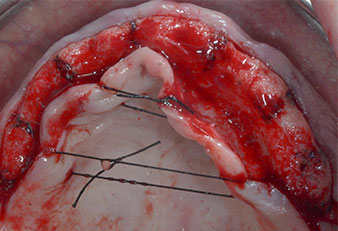

A causa dell'osso relativamente duro (D2) in quest'area, le sedi dell'impianto di 10 mm nelle posizioni 11 e 21 sono state finalizzate con un trapano rotante da 4 mm di diametro, in combinazione con un contrangolo chirurgico W&H WS-75 L, il motore per impianto W&H Implantmed e il modulo opzionale Osstell ISQ di W&H. Al contrario, a causa dell'osso morbido, le sedi posteriori sono state preparate a un diametro finale di 3 mm utilizzando lo strumento Piezomed I3P. Gli impianti sono stati infine posti per via transgengivale sull'osteointegrato per tre mesi (Figg. 6-10). La protesi dentaria esistente è stata mantenuta su quattro impianti provvisori (Fig. 8).